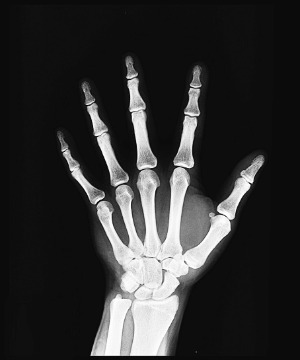

우선, 관절이란 두 개 이상의 뼈가 연결되어 움직임을 가능케 하는 부위입니다. 이는 연골, 인대, 힘줄, 관절낭 등 복합적인 구조로 이루어져 있어, 우리의 일상 움직임과 기능을 원활하게 유지하는 데 중요한 역할을 합니다.

류마티스 관절염은 주로 양쪽의 대칭적인 작은 관절을 표적으로 합니다. 손가락, 발가락의 관절, 손목, 발목, 팔꿈치, 무릎 등이 부어오르고 아프며 따끔거립니다. 이런 부음은 염증으로 인해 관절 주변의 활막이 팽창하고 관절액이 증가하기 때문입니다.